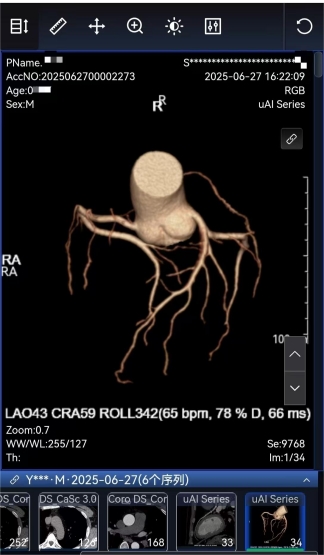

排栓前:左前降支近段管腔约中—重度狭窄 排栓后:到医院检查不符合心脏支架标准